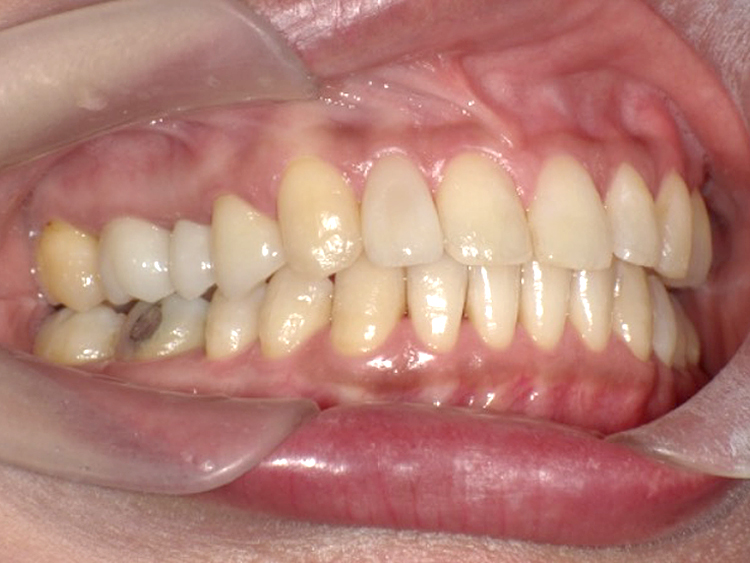

症例4

Before

After

| 主訴 | 上下前歯のがたつき |

|---|---|

| 年齢 | --- |

| 治療 期間 |

約9ヶ月 |

| 治療 内容 |

インビザラインiGoで上下顎の治療。 |

| 治療費 | ¥550,000(税込)/調整料含む |

| 治療のリスク | 矯正終了後は、リテーナーを指示通りに使用し、歯の後戻りを防ぐ必要があります。 |